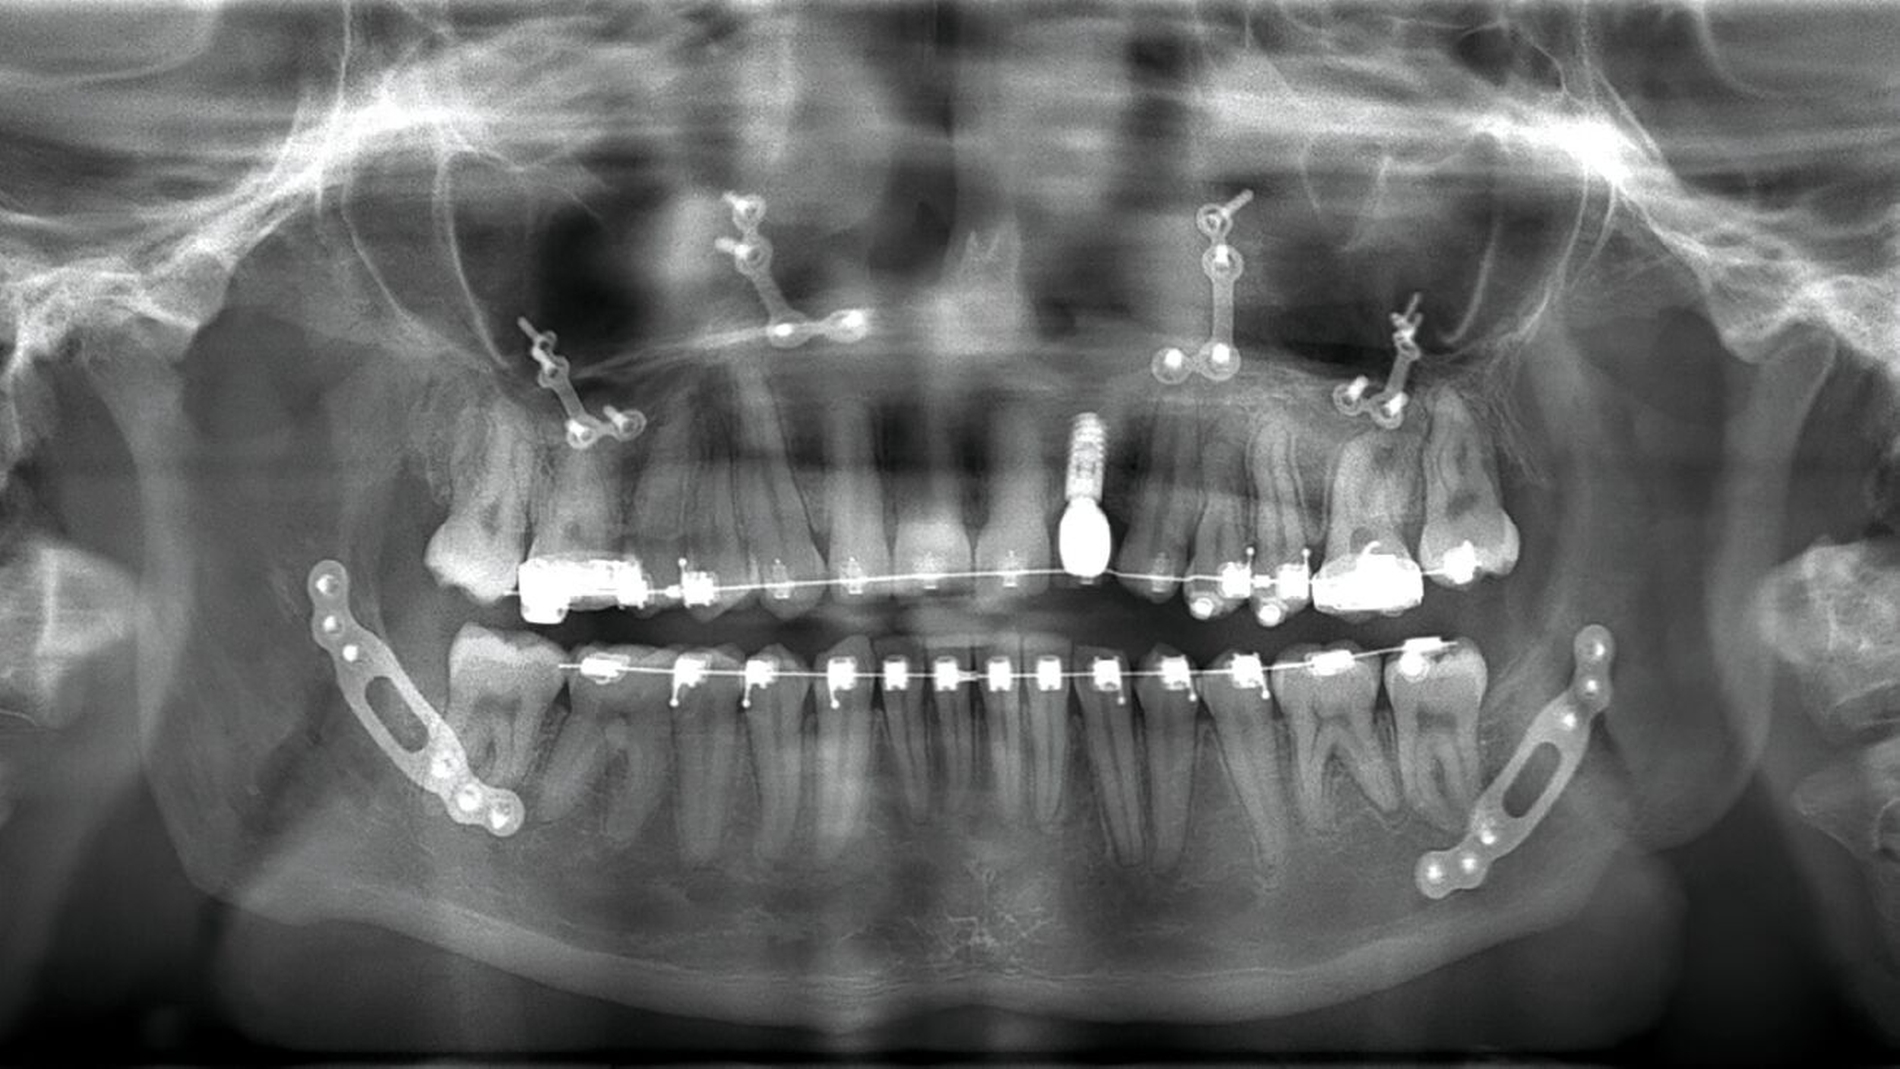

Nach diesem Eingriff schloss sich bis zum 17. Lebensjahr eine kieferorthopädische Therapie bei skelettaler maxillärer Retrognathie an. Der Zahn 22 war nicht angelegt, die Lücke wurde kieferorthopädisch offengehalten. Im Bereich 22 wurden nach Abschluss des Wachstums eine Augmentation durchgeführt und ein zahnärztliches Implantat inseriert. Dennoch konnten die Laterognathie des Oberkiefers mit einer Mittellinienverschiebung von 2,5 mm, der Tiefbiss sowie der Kreuzbiss auf der linken Seite nicht vollständig behoben werden (Abbildungen 1 und 2).

Gemeinsam mit den behandelnden Kieferorthopäden wurde aufgrund des abgeschlossenen Wachstums und der ausgeschöpften nicht-chirurgischen Maßnahmen die interdisziplinäre Indikation zur chirurgischen Korrektur der Dysgnathie gestellt. Anhand einer kephalometrischen Analyse trafen wir gemeinsam mit der Patientin die Entscheidung zur Durchführung einer bimaxillären Umstellungsosteotomie (Abbildung 3).

Der Eingriff konnte noch im selben Jahr komplikationslos in Intubationsnarkose durchgeführt werden. Nach digitaler Planung durch Matching der präoperativen DVT-Aufnahmen und der Intraoralscans wurden die Splinte für die Operation 3-D-gedruckt, nachdem die Zielokklusion festgelegt worden war. Der Oberkiefer wurde in der Le-Fort-I-Ebene osteotomiert und um 0,5 mm nach anterior und um 2,5 mm nach rechts verlagert. Durch die Kippung entstanden eine rechtsseitige dorsale Impaktierung um 1,5 mm und eine linksseitige Kaudalverlagerung um 1 mm. Der Unterkiefer wurde um 1 mm nach anterior verlagert, wobei es zu einer Schwenkung von 5 mm nach anterior links und um 2 mm nach posterior rechts kam (Abbildung 4).